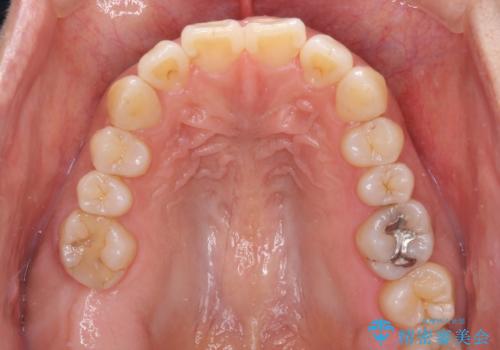

- 上下前歯の叢生を気にして来院された患者様です。

費用を抑え、期間もあまりかけずに治療をしたいとのことで、インビザライン・ライトを用いて矯正治療を行うこととしました。

インビザライン・ライトは、製作できるアライナーの枚数に制限があるため、移動可能な量に限りがあります。

一方で、半年から1年程度で治療を終えることができるため、軽度の歯列不正の患者様には大変お勧めです。